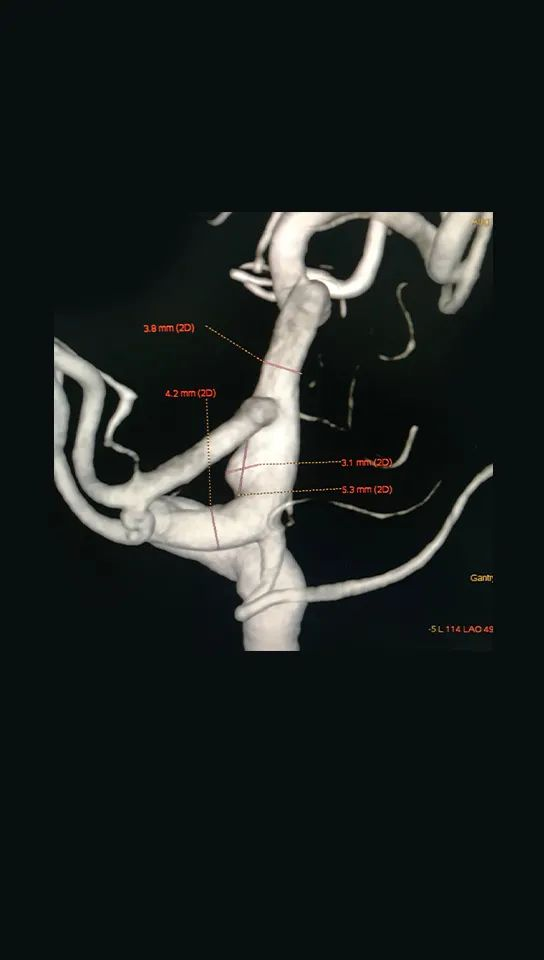

头颅CTA显示“蛛网膜下腔出血,右侧颈内C7段瘤样扩张”

Navien + Phenom助力上高到颈内动脉末端

回撤到平直段,半释放pipeline

Navien继续上高,推支架,确保瘤颈处支架的贴壁